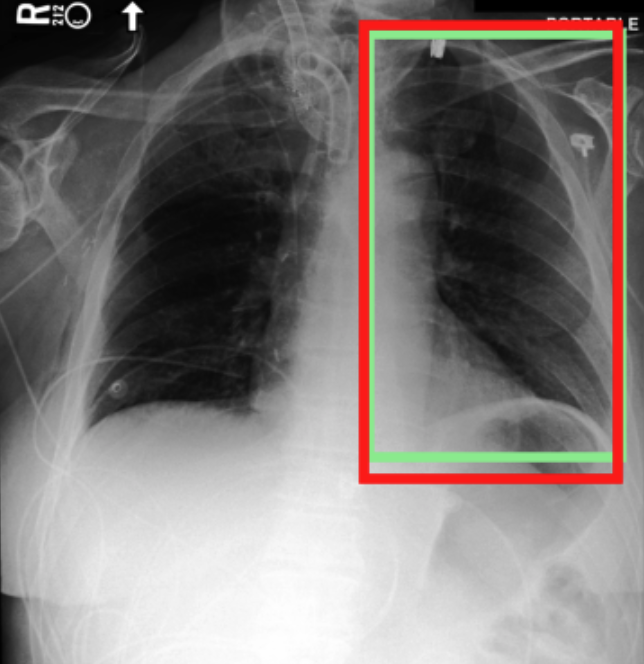

4.3.3 Visual grounding

In this section, we evaluate RadVLM’s visual grounding capabilities, which could help clinicians localize specific regions or pathologies on a CXR. This is particularly useful once a pathology has already been identified – either by a radiologist’s input or through our previously described AI tasks – since it allows one to pinpoint exactly where the abnormality appears on the image.

We report performance metrics for the three main grounding tasks RadVLM was trained on: anatomical grounding using the Chest Imagenome test set, abnormality grounding using the VinDr-CXR test set, and phrase grounding using the MS-CXR test set (Table 1). For each task, we use mean Average Precision (mAP) as our primary evaluation metric.

Our results show that RadVLM performs well at localizing anatomical regions (e.g., “right lung”, “aortic arch”, illustrated in Figure 5a), achieving a mAP of 85.8 %, by far surpassing the other CXR grounding models (Table 4). This advantage is partly explained by including the Chest Imagenome dataset (and thus the anatomical grounding task) in the training set, which CheXagent and MAIRA-2 did not leverage. However, it remains a key feature for any grounding model to possess a fine-grained understanding of CXR anatomy.

For the abnormality grounding task, RadVLM is less consistent (Figure 5b), likely due to higher sparsity of abnormality locations and labels, yet it still achieves best performance (Table 4). For the phrase grounding task, while MAIRA-2 and CheXagent demonstrate great performance, RadVLM surpasses them with a mAP of 81.8% (Table 4), presumably benefiting from the newly released PadChest-GR dataset (Castro et al.,, 2024) used for training.

Overall, these results show that our instruction tuning strategy for visual grounding (covering three essential tasks), combined to a modern VLM backbone, offers a promising avenue to help clinicians localize anatomical and pathological features during a CXR exam. Furthermore, providing fine-grained details within an LLM-generated output may also enhance the ability to answer grounded questions in a multi-turn setting, as we explore next.